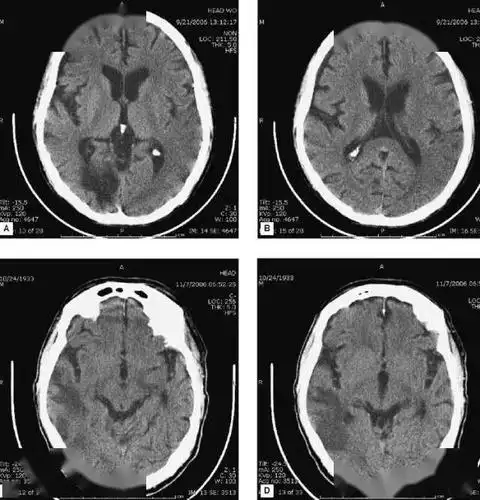

67超急性期大面积脑梗死ct平扫表现

图19:2015-4-19 ct:脑室系统正常